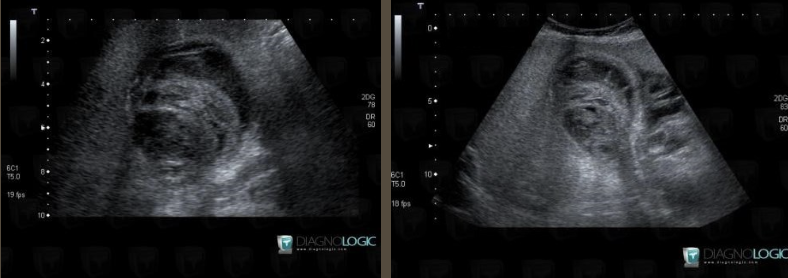

Acute Pancreatitis → sudden inflammation of pancreas from blockage of ducts and increased secretions

2D US: pancreas enlargement, hypoechoic parenchyma from edema, irregular ill-defined borders, peripancreatic free fluid, peripancreatic echogenic inflammatory fat, can have focal areas of inflammation/hypoechoic tissue

Pancreatic Pseudocyst → peripancreatic fluid collection from trauma or pancreatitis (4-6 week onset after pancreatitis)

2D US: not always spherical, usually located in lesser sac (anterior to pancreas and posterior to stomach)